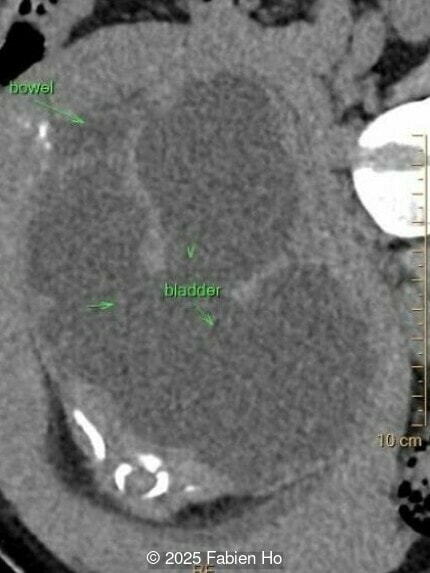

Our prenatal ultrasound revealed a male fetus with megabladder, dilation of both ureter and kidneys, and thinned kidney parenchyma consistent with Lower Urinary Tract Obstruction (LUTO). Additional findings suspected on ultrasound and confirmed on computed tomography included:

- Suspicion of dilated bowel in the left flank, in addition to dilated urinary tract

The diagnosis of PBS is often made in the second trimester of pregnancy, although it has been described as early as 11 weeks of gestation [20]. The most frequent ultrasound findings are a large, thin-walled bladder accompanied by bilateral hydroureter/hydronephrosis, dysplastic kidneys with echogenic renal parenchyma and renal cortical cysts, and abdominal wall laxity which is better viewed after bladder decompression [21]. Cryptorchidism can be detected prenatally by 28 to 30 weeks gestation when the testes descend into scrotum. There may be a patent urachus, visible as a cystic connection between bladder and umbilicus. Oligohydramnios is a frequent finding, which makes it difficult to visualize the associated anomalies.